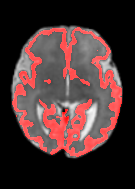

Fetal cortical plate segmentation is essential in quantitative analysis of fetal brain maturation and cortical folding. Manual segmentation of the cortical plate, or manual refinement of automatic segmentations is tedious and time-consuming. Automatic segmentation of the cortical plate, on the other hand, is challenged by the relatively low resolution of the reconstructed fetal brain MRI scans compared to the thin structure of the cortical plate, partial voluming, and the wide range of variations in the morphology of the cortical plate as the brain matures during gestation. To reduce the burden of manual refinement of segmentations, we have developed a new and powerful deep learning segmentation method. Our method exploits new deep attentive modules with mixed kernel convolutions within a fully convolutional neural network architecture that utilizes deep supervision and residual connections. We evaluated our method quantitatively based on several performance measures and expert evaluations. Results show that our method outperforms several state-of-the-art deep models for segmentation, as well as a state-of-the-art multi-atlas segmentation technique. We achieved average Dice similarity coefficient of 0.87, average Hausdorff distance of 0.96 mm, and average symmetric surface difference of 0.28 mm on reconstructed fetal brain MRI scans of fetuses scanned in the gestational age range of 16 to 39 weeks. With a computation time of less than 1 minute per fetal brain, our method can facilitate and accelerate large-scale studies on normal and altered fetal brain cortical maturation and folding.